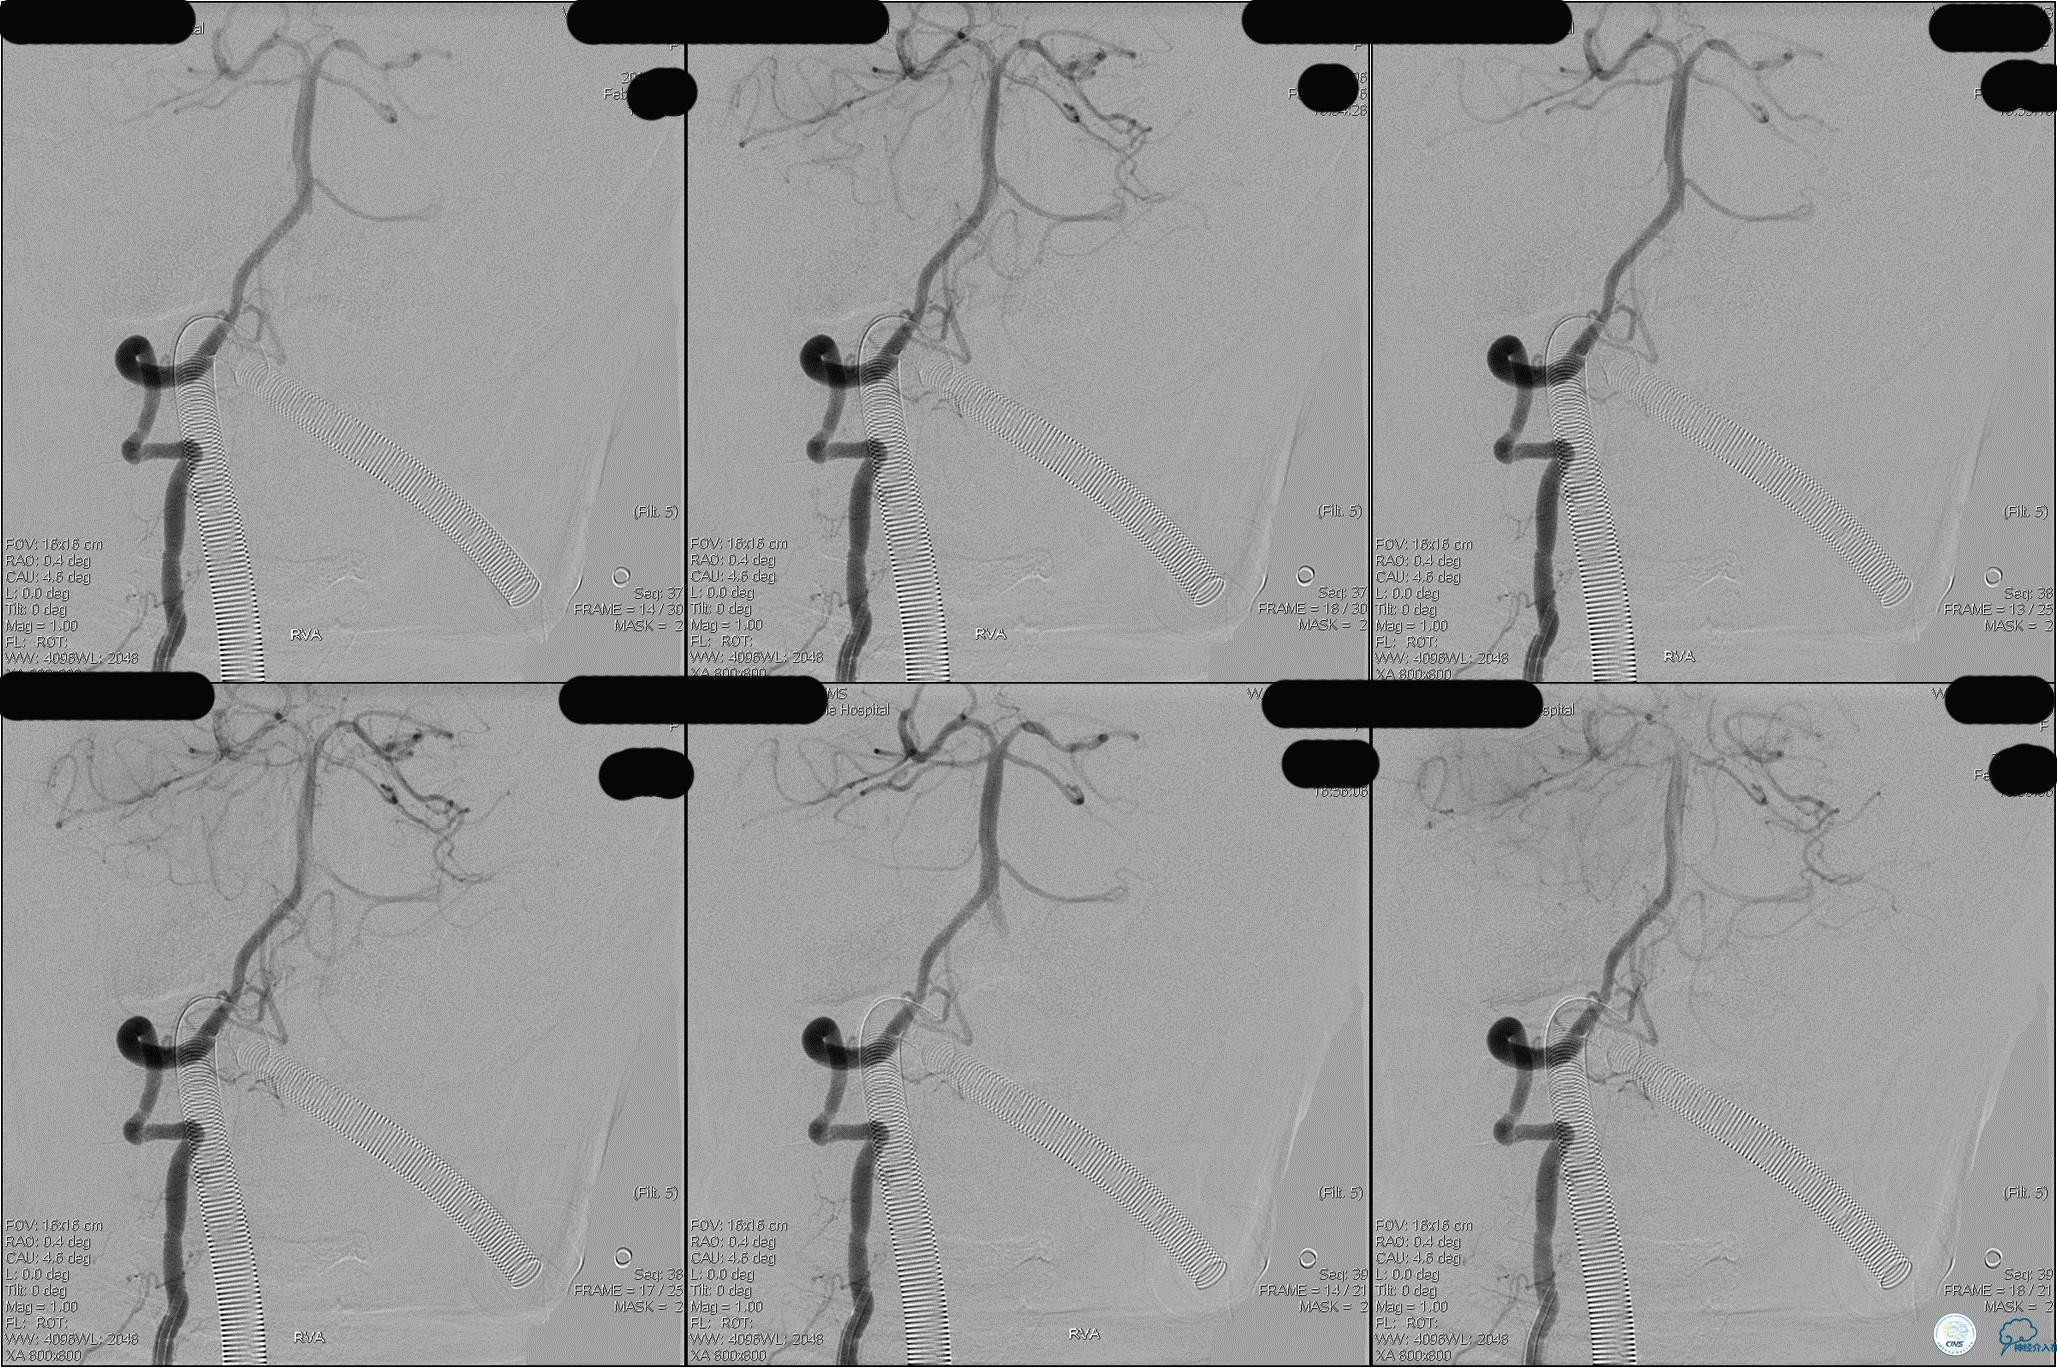

》DSA资料(第3次取栓后,发病10h)

》DSA资料(观察30min后,左椎造影)

★后循环取栓病人,若股动脉入路较差,可以考虑经桡动脉进行。

★基底动脉尖端的血栓偏向哪侧,应该将Solitaire支架放入同侧的大脑后动脉,这样取栓的成功率较高一些。